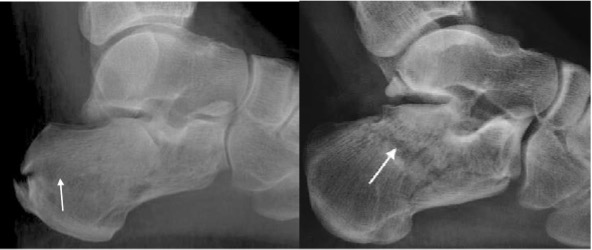

Calcaneal fracture

Usually from a fall from height

Extra-articular: 25-30%

- Anterior calcaneal process fracture, calcaneal tuberosity avulsion, extra-articular body fracture, sustentaculum

Intra-articular: 70 – 75%

- Usually comminuted

- ‘Double density’ sign due to impacted fracture, subtalar incongruity and separation of sustentaculum

- Decreased Bohler’s angle <20°

- Increased Gissane angle >145°

- Shear fracture in sagittal plane splits calcaneus into anteromedial (sustentacular) and posterolateral (tuberosity) fragments.

- Compression fracture in coronal plane with anterior limb running through critical angle of Gissane and posterior limb extending either horizontally in axial plane toward the tuberosity in tongue type fracture or more vertically, behind the posterior facet in joint depression type fracture.

- Look for lateral malleolar ‘fleck’ sign which raises likelihood of peroneal tendon instability.

Calcaneal fracture: tongue type Calcaneal fracture: joint depression type